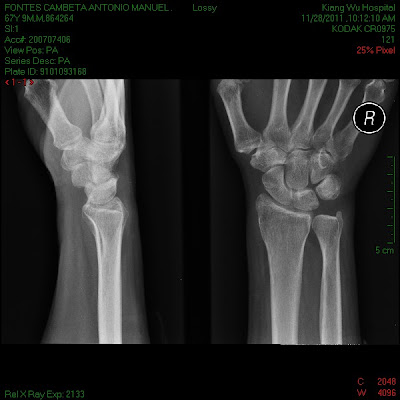

Esta manhã o articulista acordou com imensas dores na mão direita e no ombro esquerdo, os medicamentos que lhe foram receitados, ontem, no Hospital Central Conde de S. Januário não aliviaram em nada as dores, e como só tem consulta marcada para dia 12 de Dezembro, o articulista, telefonicamente marcou uma consulta com o médico Ortopedista no Hospital de Kiang Wu, e após tomar o pequeno almoço seguiu para o referido hospital.

Não demorou muito tempo a ser ocultado pelo médico, tendo o mesmo informado que teria que tirar algumas radiografias para ver o problema mais a fundo.

A mão direita não apresentava qualquer factura, simplesmente, e segundo informção médica, havia um nervo inflamado.

No raioX feito à coluna, aí o problema era bem visível, a quarta vertebra cervical se encontrava como se pode ver, o que necessita de tratamento mais profundo.

Pelas radiografias tiradas o articulista pagou a quantia de 501,00 patacas, cerca de 50 euros.